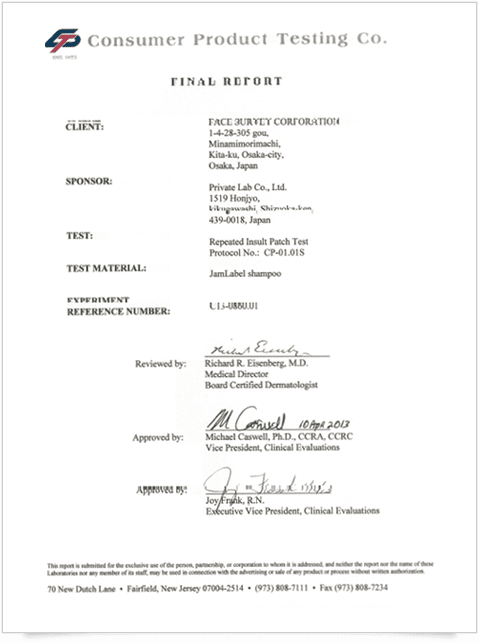

厳しい試験をすべてクリア。

厳しい試験を

アメリカの医学博士、

敏感肌・トラブル肌の方にも

ファイナルレポートの 実証証明書 -

刺激反応なしを表す オールゼロの検証結果